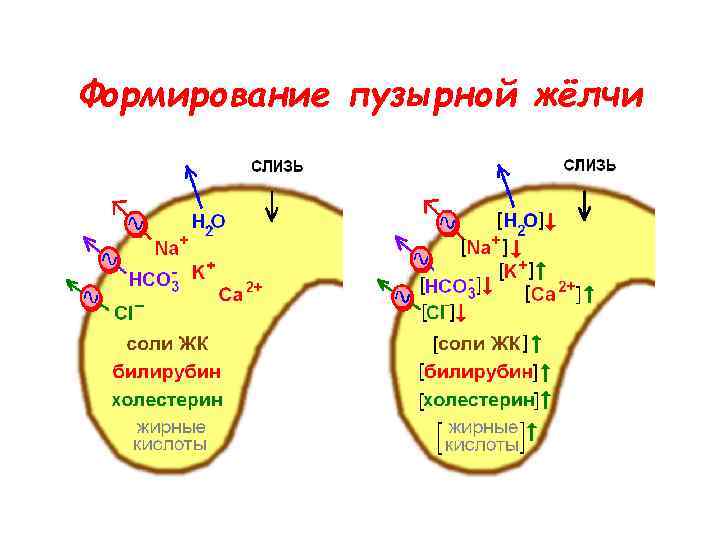

Формирование пузырной жёлчи

Формирование пузырной жёлчи

Формирование пузырной жёлчи

Формирование пузырной жёлчи

Состав печёночной и пузырной жёлчи

Состав печёночной и пузырной жёлчи